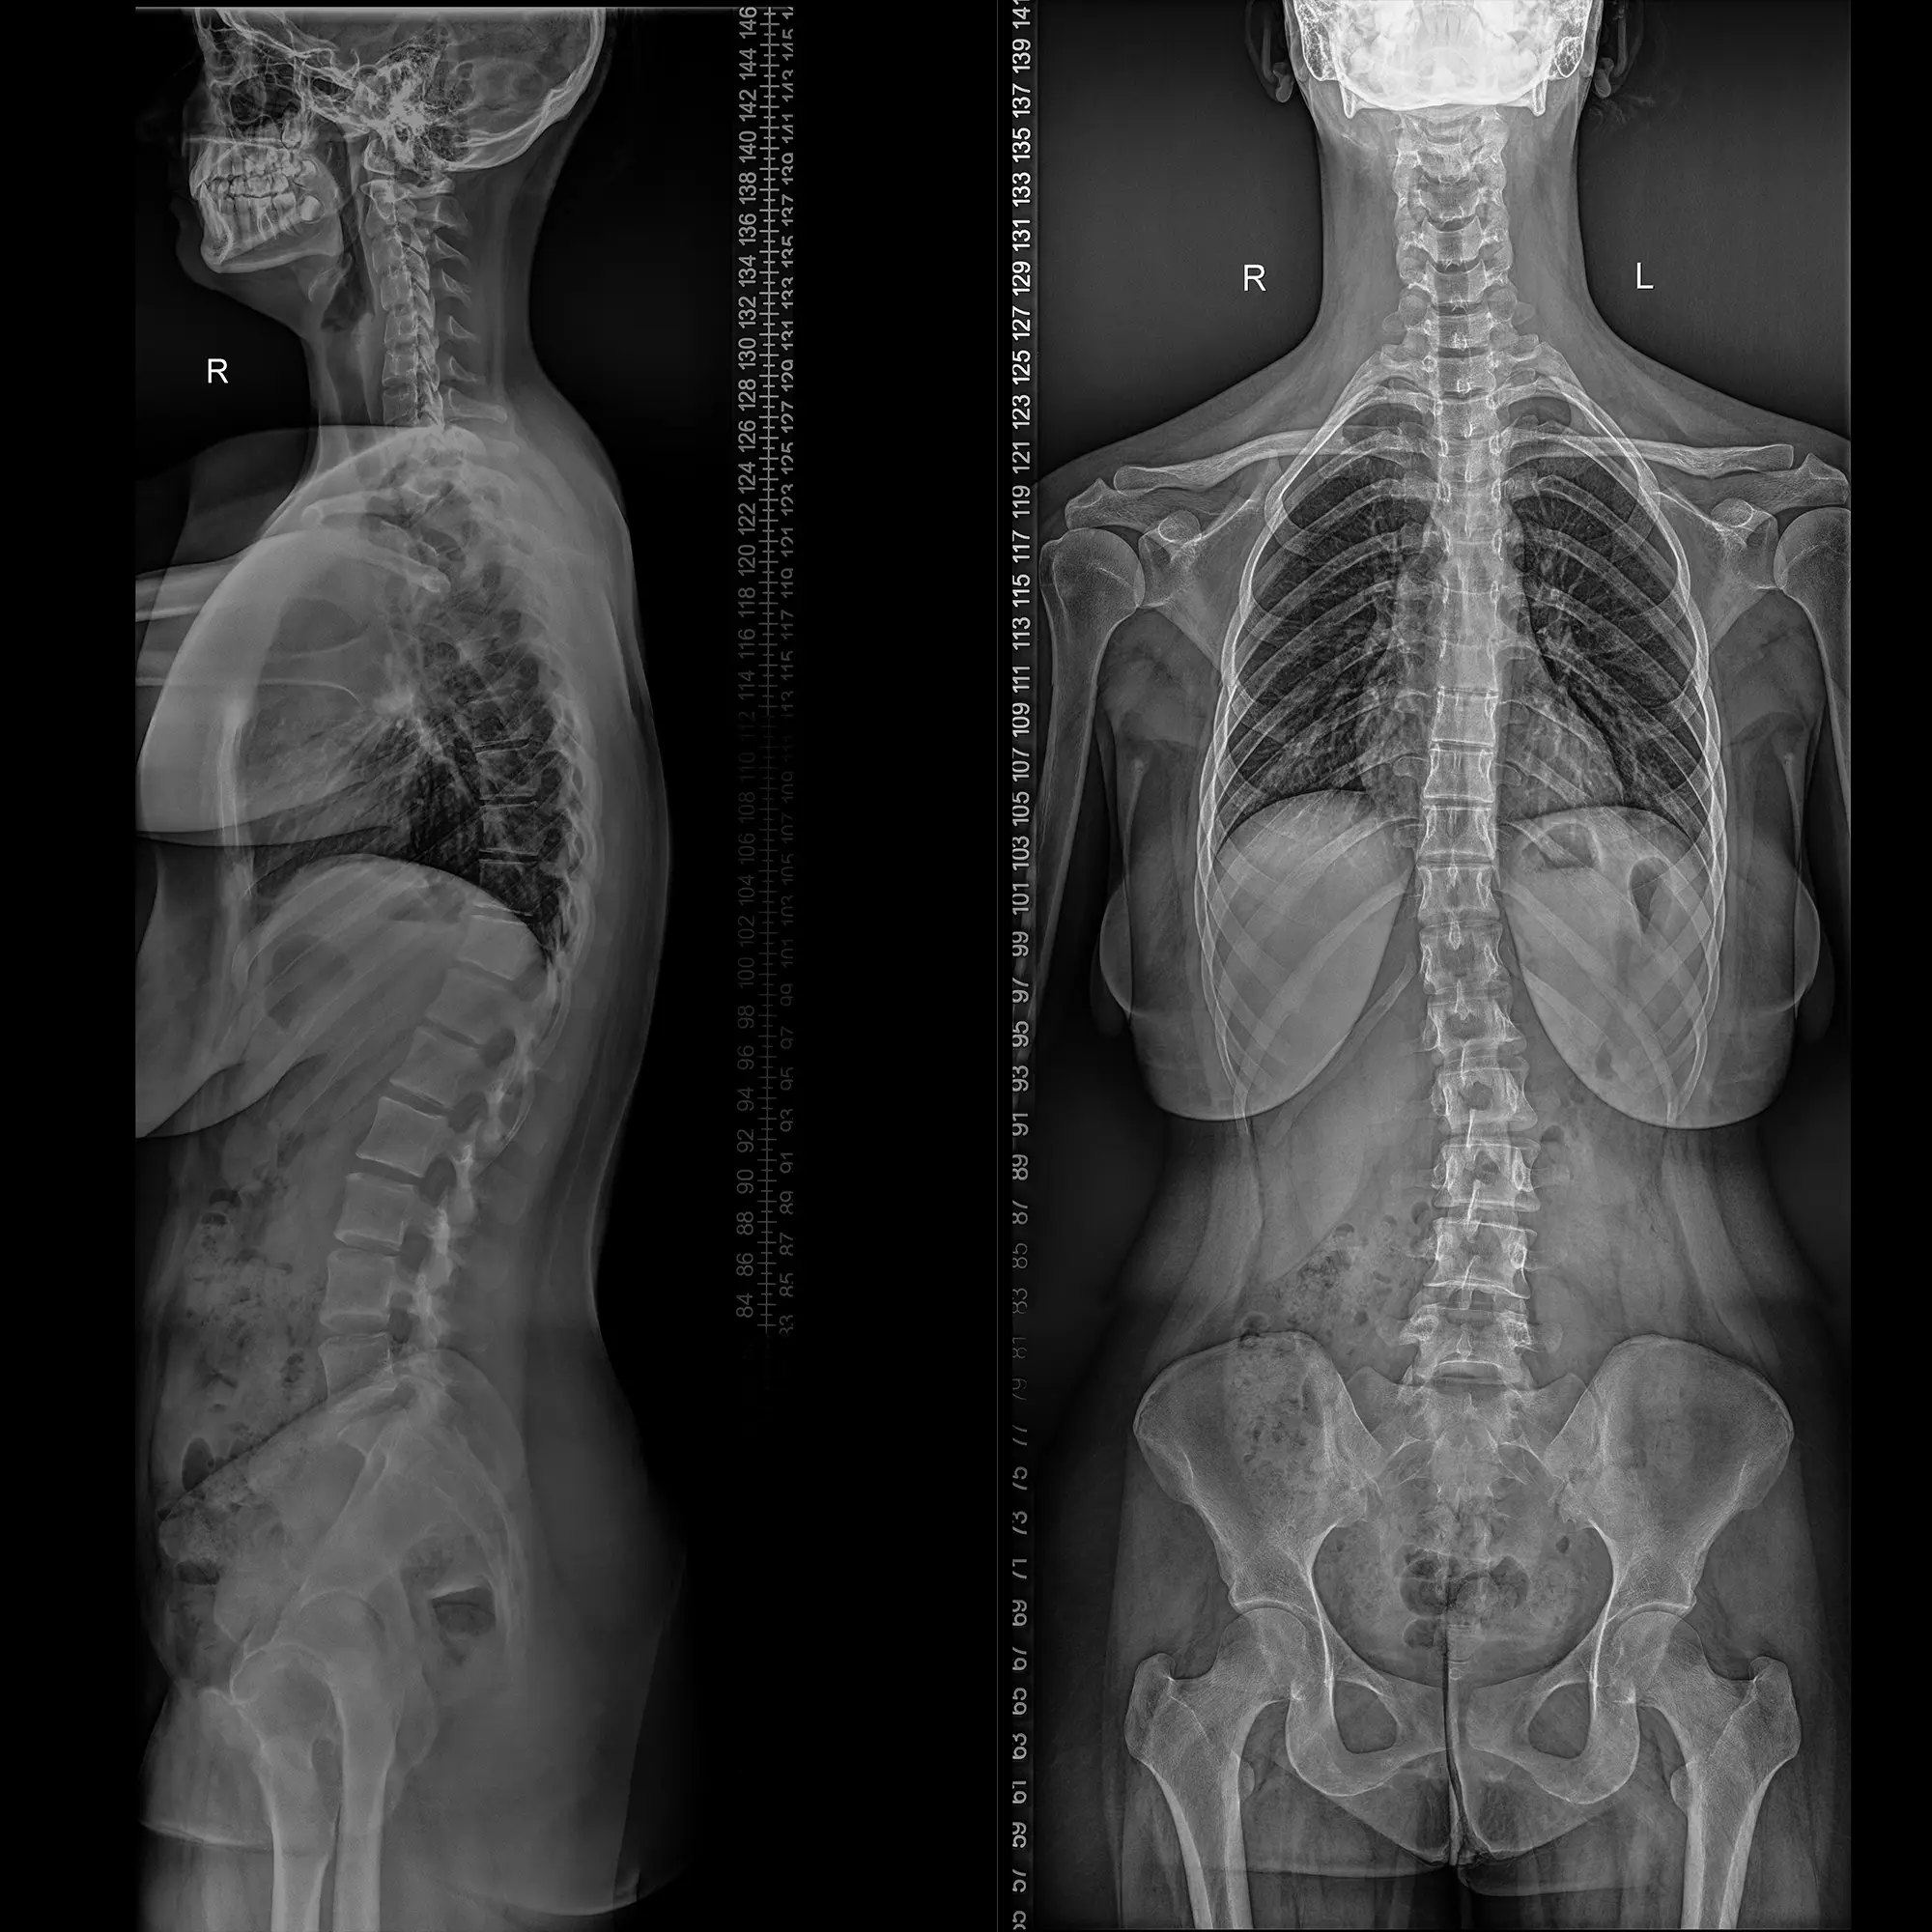

Ortospine este o tehnologie specializată în evaluarea coloanei vertebrale, utilizată pentru a diagnostica și monitoriza diverse afecțiuni ale acesteia, în special cele scoliotice. Ortospine folosește tehnologia de teleradiografie, ceea ce înseamnă că poate oferi o imagine completă și detaliată a coloanei vertebrale într-o singură captură.

DRX EVOLUTION PLUS, produs de CARESTREAM, este un aparat de radiologie generală ce realizează investigații 2D (radiografii).